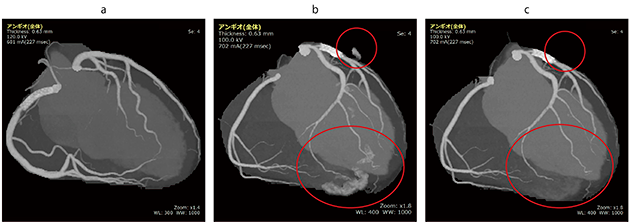

上記課題を解決すべく,VINCENT V5に搭載している冠動脈抽出エンジンでは,線量低下や低管電圧撮影によるSNRの低い画像に対し,冠動脈以外の誤抽出を防ぐ改良を追加した(図1)。

図1 低管電圧で撮影されたCT画像を異なるバージョンで実施した時の抽出結果例

aはb,cと異なる症例である。

a:管電圧120kv。撮影の画像例。一般的な管電圧で撮影されたデータに対して過抽出は少ない。

b:管電圧100kv。撮影の画像をV4.6で抽出した画像例。冠静脈,心筋などの過抽出が目立つ(○)。

c:管電圧100kv。撮影の画像をV5で抽出した画像例。冠動脈以外の過抽出が大幅に減少している。